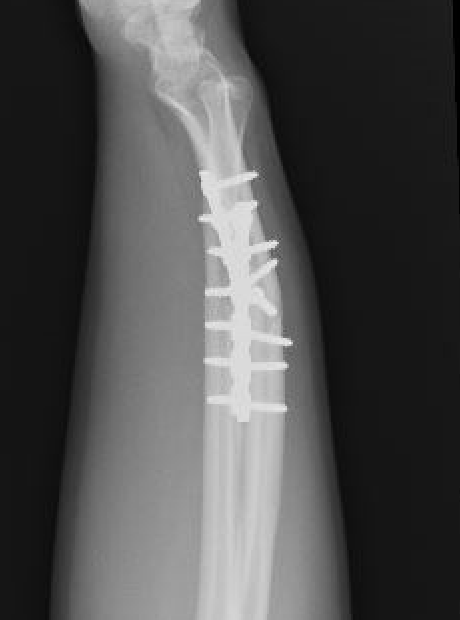

Galeazzi fracture

Galeazzi fracture with DRUJ disruption

Incidence of DRUJ instability after radius ORIF

Rettig et al J Hand Surg Am 2001

- 40 patients with Galeazzi fracture dislocations

- DRUJ instability after radius ORIF

- Type 1: radius fracture < 7.5 cm to articular surface: 55% DRUJ instability

- TYpe II: radius fracture > 7.5 cm to articular surface: 6% DRUJ instability